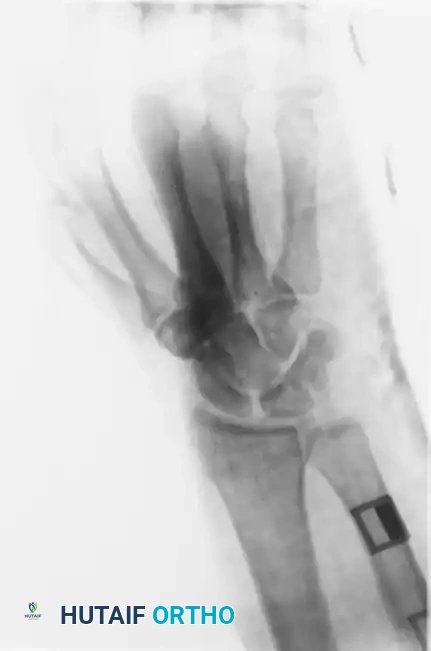

Standard posteroanterior (PA), lateral, and oblique radiographs are mandatory. However, the overlapping anatomy of the carpus can obscure subtle subluxations.

FIGURE 67-30 B-D: Posteroanterior, Lateral, and Oblique radiographic views demonstrating the dorsal dislocation of the fourth and fifth carpometacarpal joints.